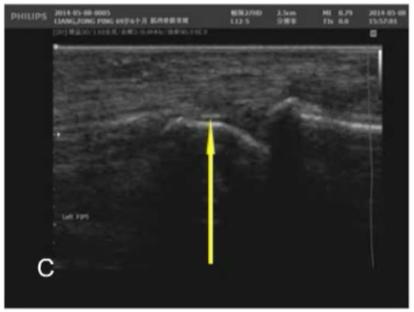

图6:腕关节内可见点状高回声

图7:掌指关节软骨表面可见线状高回声,提示“双轨征”苏茵主任指出,在关节超声表现下出现“双轨征”提示“尿酸盐的结晶”。